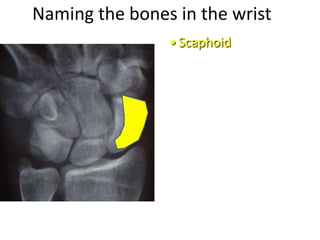

This document provides an overview of hand anatomy including:

- Naming the bones, joints, tendons, nerves and skin landmarks of the hand and wrist.